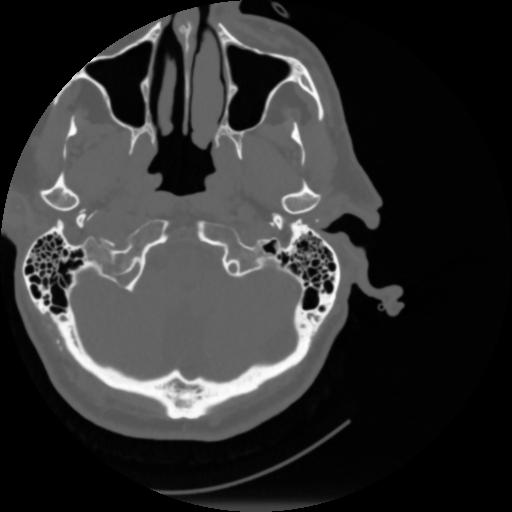

4 CEREBRO,,Vol,0.5,CEREBRO,,